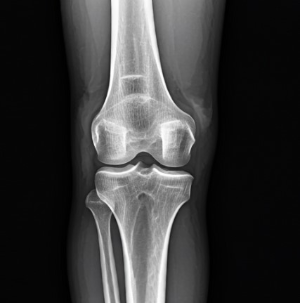

연골은 관절을 부드럽게 움직일 수 있도록 도와주는 쿠션 역할을 합니다. 그러나 나이가 들수록 연골은 자연스럽게 닳거나 손상되면서 관절의 마찰과 통증을 유발하게 됩니다. - 근육량 감소

특히 계단을 내려갈 때 무릎에 더 큰 부담이 가해져 통증이 심해질 수 있습니다. 이는 무릎 연골이 약해졌거나 손상되었음을 시사합니다. - 오랫동안 앉아 있다가 일어날 때 느껴지는 뻣뻣함

관절에서 '딸깍' 소리나 '삐걱' 소리가 자주 들리는 것은 관절 간 마찰이 증가했음을 나타낼 수 있습니다. 이는 연골의 손상이나 관절액 부족과 관련이 있습니다. - 가벼운 운동 후에도 오래 지속되는 통증

Q3: 관절염과 단순 관절 통증은 어떻게 구별하나요?

A: 관절염은 부종, 열감, 지속적인 뻣뻣함이 동반되며, 단순 통증은 휴식 후 완화됩니다.